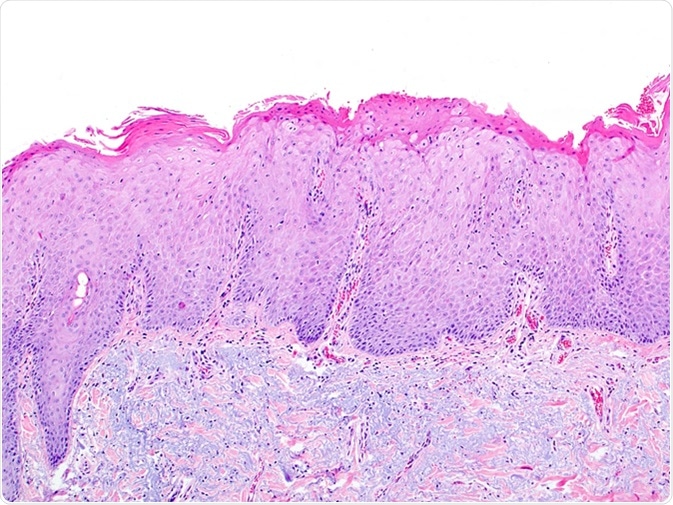

Skin biopsy showing solar elastosis and actinic keratosis due to exposure to UV rays, excessive sun exposure. The dermal region contains elastic blue fibers and the epidermis is irregularly thickened. Image Credit: vetpathologist / Shutterstock

The diagnosis of solar elastosis is clinical supplemented by biopsy from the affected area. This shows loss of eosin staining in the upper skin layers resulting in a blue stain, with the appearance of grossly disorganized elastin fibers in the dermis. Treatment should be timely.